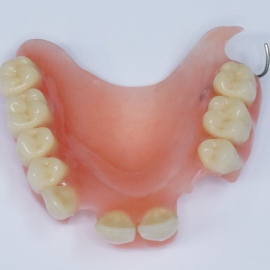

Pacjentka lat 58, prowadzi aktywne życie zawodowe. Odczuwała dyskomfort przy użytkowaniu protezy, dodatkowo przy uśmiechu odsłaniała klamry utrzymujące protezę.

Pacjentka lat 68, prowadzi aktywny tryb życia, dużo podróżuje, przeszkadzały jej klamry widoczne na zębach przy uśmiechu, oraz słaba stabilność protezy, co powodowało dyskomfort przy użytkowaniu.

Pacjentka prowadzi aktywne życie zawodowe, niedawno zakończyła leczenie ortodontyczne, niestety nie nastąpiło po nim właściwe leczenie protetyczne. Użytkowała protezę ruchomą z klamrami dziąsłowymi.

Hybrydowe podparcie protezy ruchomej na jednym implancie i jednym własnym zębie. Nie zawsze możemy osadzić u pacjenta dwa implanty. Przykłady hybrydowego podparcia protezy ruchomej na atachmentach opartych na własnym zębie i implancie.